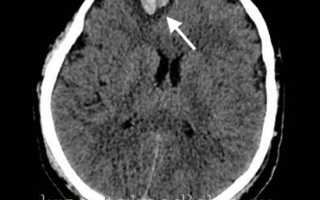

Основным методом диагностики ушибов головного мозга (УГМ) является компьютерная томография (КТ). Томографическая картина зависит от тяжести ушиба. При легкой степени очаги с пониженной плотностью выявляются лишь в 40-50% случаев. В зоне ушиба на томограммах отмечаются отечность и петехиальные кровоизлияния. Отек может охватывать всю долю мозга или даже полушарие, что приводит к умеренному сужению ликворных пространств.

На аксиальной КТ головного мозга без контрастного усиления определяется контузионный очаг в правой лобной доле, представленный геморрагическим компонентом, зоной детрита и отека.

Ушиб средней тяжести характеризуется наличием очагов ушиба в виде зон пониженной плотности. При геморрагическом пропитывании очаг может иметь повышенную плотность. При тяжелом ушибе томография визуализирует очаги как повышенной, так и пониженной плотности: сгустки крови определяются как участки повышенной плотности, а размозжение и отек — как участки пониженной плотности. При крайне тяжелых поражениях зона деструкции церебральной ткани может затрагивать подкорковые структуры.